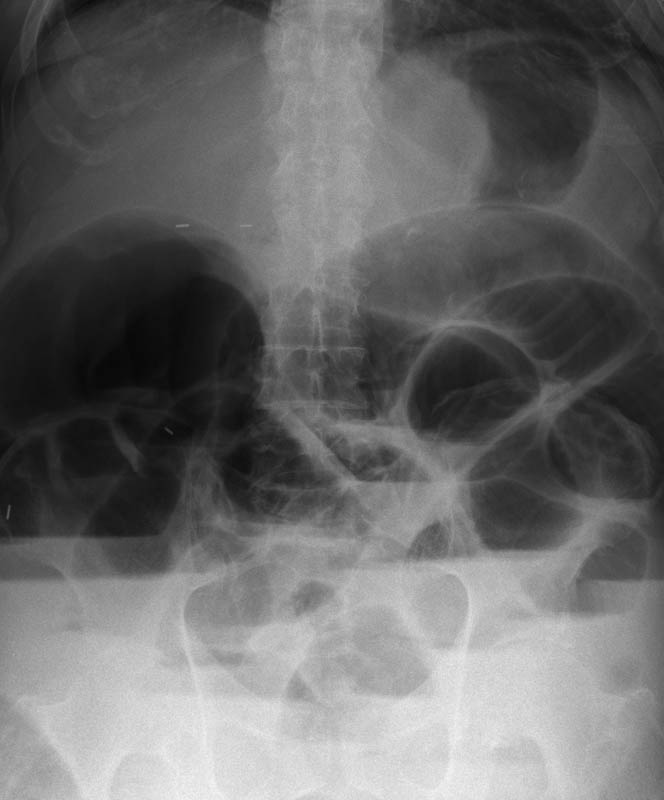

Diverticulosis de colon.

Diverticulosis de colon. Megacolon.

Dolico-megacolon.